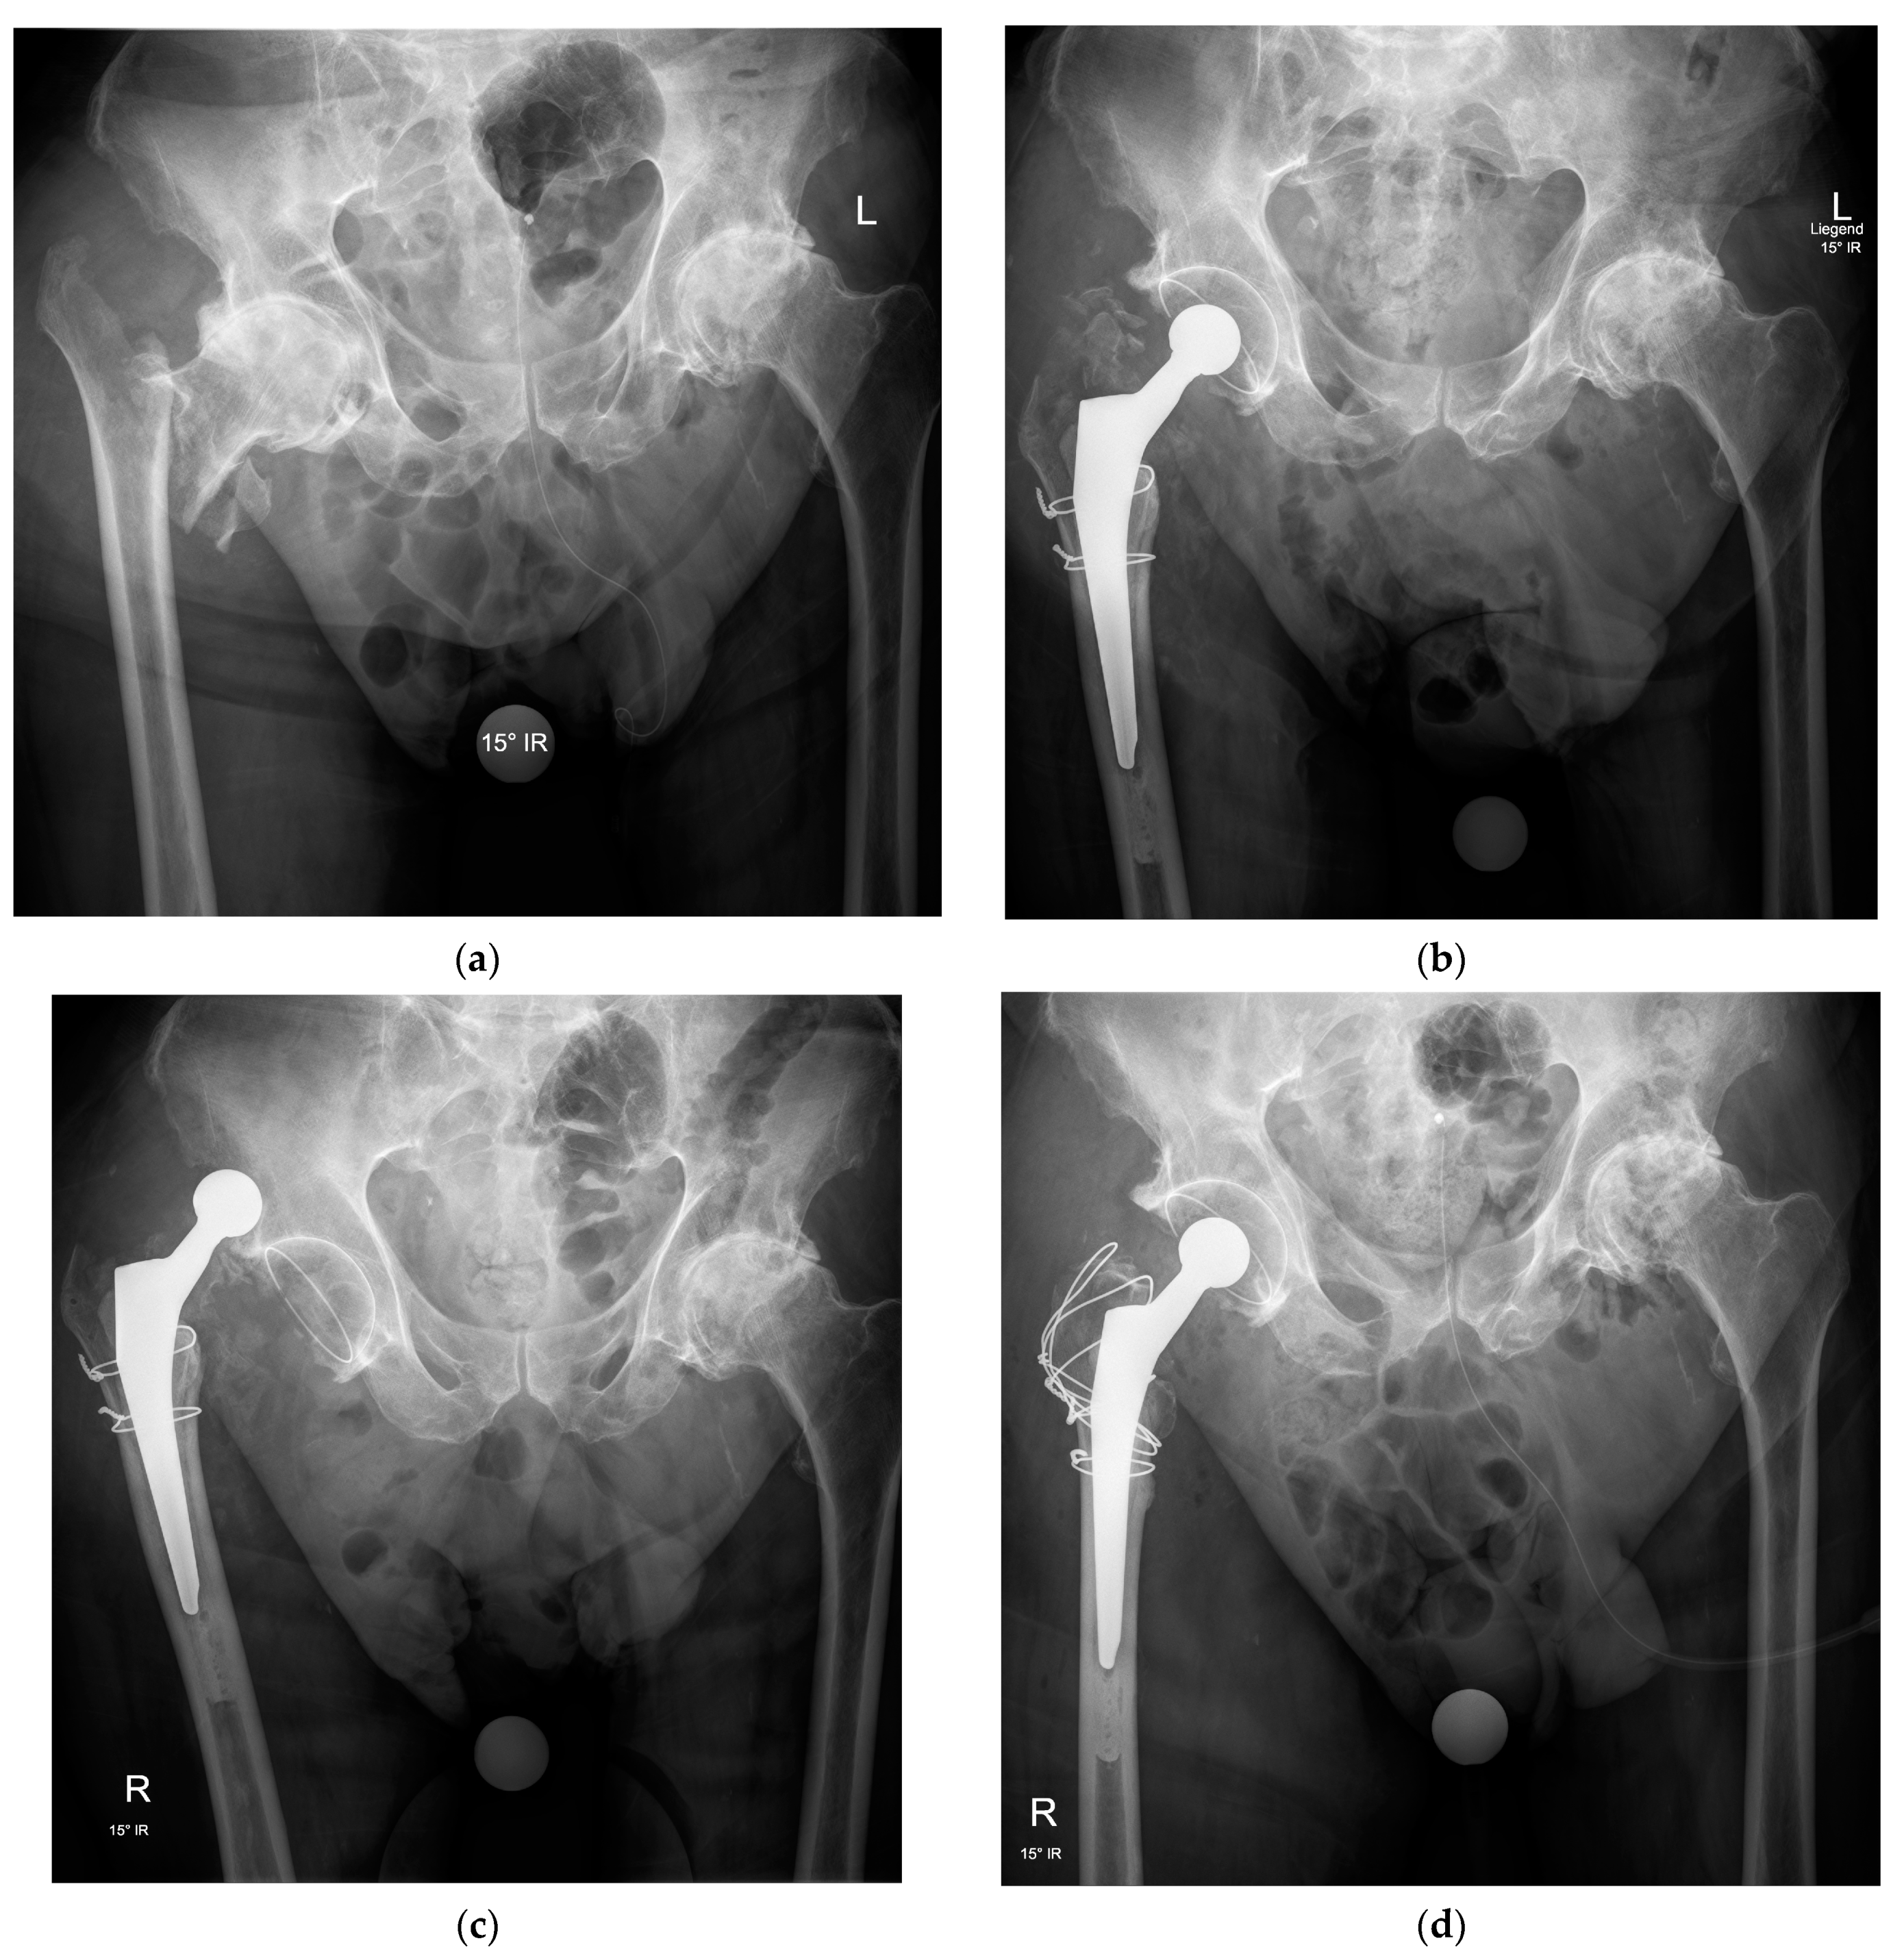

Many IFFs leave the greater trochanter as a separate fragment. Considering its importance for proper functioning of the hip joint, appropriate treatment is mandatory. Adequate reduction and fixation of the trochanter fragment improves the stability of the prosthesis and restores the tension in the gluteus medius (Figure 3).

Figure 3.

Anteroposterior pelvic radiographs of an intertrochanteric fracture with advanced osteoarthritis (a) treated by total hip arthroplasty with a cemented femoral stem, a cemented acetabular cup, and two wire cerclages to stabilize the metaphyseal fragments around the femoral stem but without fixation of the greater trochanter (b), resulting in recurrent dislocations in the early postoperative period (c) and requiring revision surgery for fixation of the greater trochanter by a figure-of-eight wire cerclage technique allowing restoration of hip stability and healing of the fracture fragments in a good position with no further dislocation (d).

The choice of the fixation technique mainly depends on the surgeon’s habits, fracture characteristics, and bone quality. Several methods are available. Wire or cable cerclage are viable options if fragment size and bone quality are sufficient. A cerclage with non-absorbable sutures is preferred if the fragments are very small, comminuted, or if the bone quality is poor. There are different types of trochanteric plates, but these are generally thick and can cause irritation and pain. Finally, some prosthesis designs include a claw-like attachment to stabilize the greater trochanter [22].